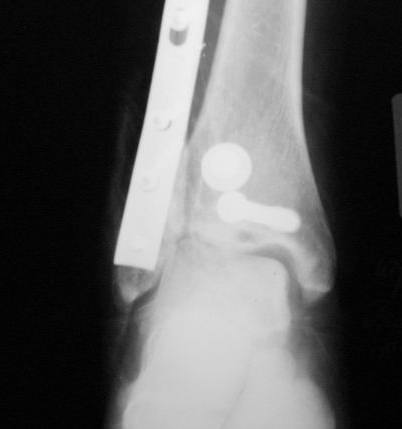

Re: Консолид. перелом г/ стопного

послал Алексей Минервин 16 Март 2006, 17:06

Уважаемые коллеги! Как и обещал, представляю плоды своей работы. Хвалиться особо нечем. Пошли задним

доступом сначала к м/берцовой кости, благодаря смещению линию перелома удалось сразу дифференцировать и по ней узким долотом (без молотка) мобилизовали отломки. Затем выделили задний край, там было проще пройти по линии перелома. Далее пластина по задней поверхности в дистальный отломок, винт проксимальнее пластины и дистрактором с трудом растянули отломки, ощущение было идеальной репозиции м/берцовой кости( доступен осмотр по задней и наружной поверхности), далее винты стандартно. Кстати, положение больной на боку: очень неудобно, но по-другому потом не повернуть на спину, чтобы сделать снимки в стандартных проекциях (ЭОПа нет). Затем дистрактор (два полукольца, спицы), репозиция заднего края, спонгиозный винт с шайбой, слишком проксимально, поэтому + еще один. Доступ к дельтовидной связке: рубец в передней порции, частично иссечен, шов. В общем, длительность операции 3,5 часа, а сказать, что все задуманное получилось, не могу.

А.Минервин.